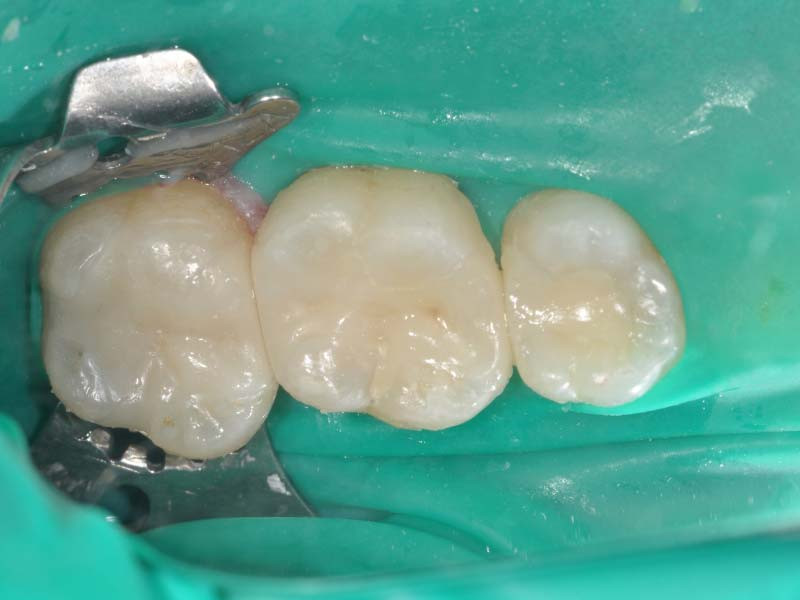

Before

牙齒蛀牙範圍大且深

After

最後用密合度高的3D齒雕復形